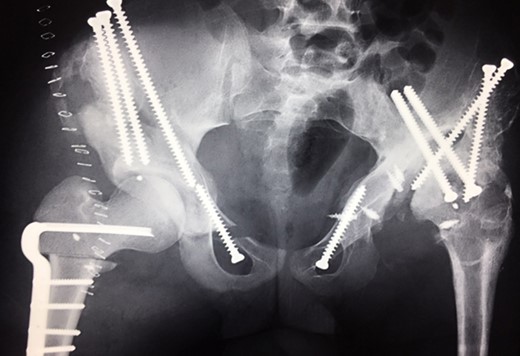

Ten years ago, a 12-year-old male presented to our clinic complaining about limping and massive swelling of the left hip. Figure 1 shows the initial X-ray and the 3D reconstruction of the left hip at first presentation when the femoral head, had already destroyed the lateral edge of the acetabulum like a mortar. Severe pain episodes have apparently not been noticed and a former hip dysplasia was not known. A brief clinical history revealed that the patient presented repeated episodes of finger biting and fevers from 2 to 8 years old. The intelligence level of the patient was at an average. The patient was admitted to a paediatric neurologist and a genetic test. A mutation of the NTRK1 gene was found and the diagnosis of CIPA was established. The right hip initially appeared to be normal and the patient was walking, therefore surgical reconstruction for the left hip was proposed due to massive swelling, inability of normal walking and significant limb length discrepancy. A Tönnis/Kalchschmidt triple pelvic osteotomy with open reduction and a shortening varus derotation osteotomy (VDRO) of the femur was performed (Fig. 2A–B). After 3 months the patient was walking again but another 3 months later the hip dislocated again without severe pain. Although the femoral head was already damaged the hip joint was reconstructed again by open reduction, capsular reconstruction with suture anchors and a trevira tube and a movable external fixator was used to temporary stabilize the joint (Fig. 3). The right hip at this time was still intact and was protected with a pneumatic orthotic device. A few months later in 2009, despite all surgeries, the left hip had entirely lost congruency and the right hip developed subluxation despite conservative treatment (Fig. 4). The patient was still walking so the decision to reconstruct the right hip with open reduction, capsular augmentation with a trevira tube, a triple pelvic osteotomy and VDRO was made (Fig. 5). Few months later this reconstruction failed as well and the hip dislocated without severe pain (Fig. 6).

(2009) Operative reconstruction of the right hip with open reduction, capsular reconstruction with trevira tube augmentation, triple osteotomy and DVO of the proximal femur to prevent destructive degeneration was performed.